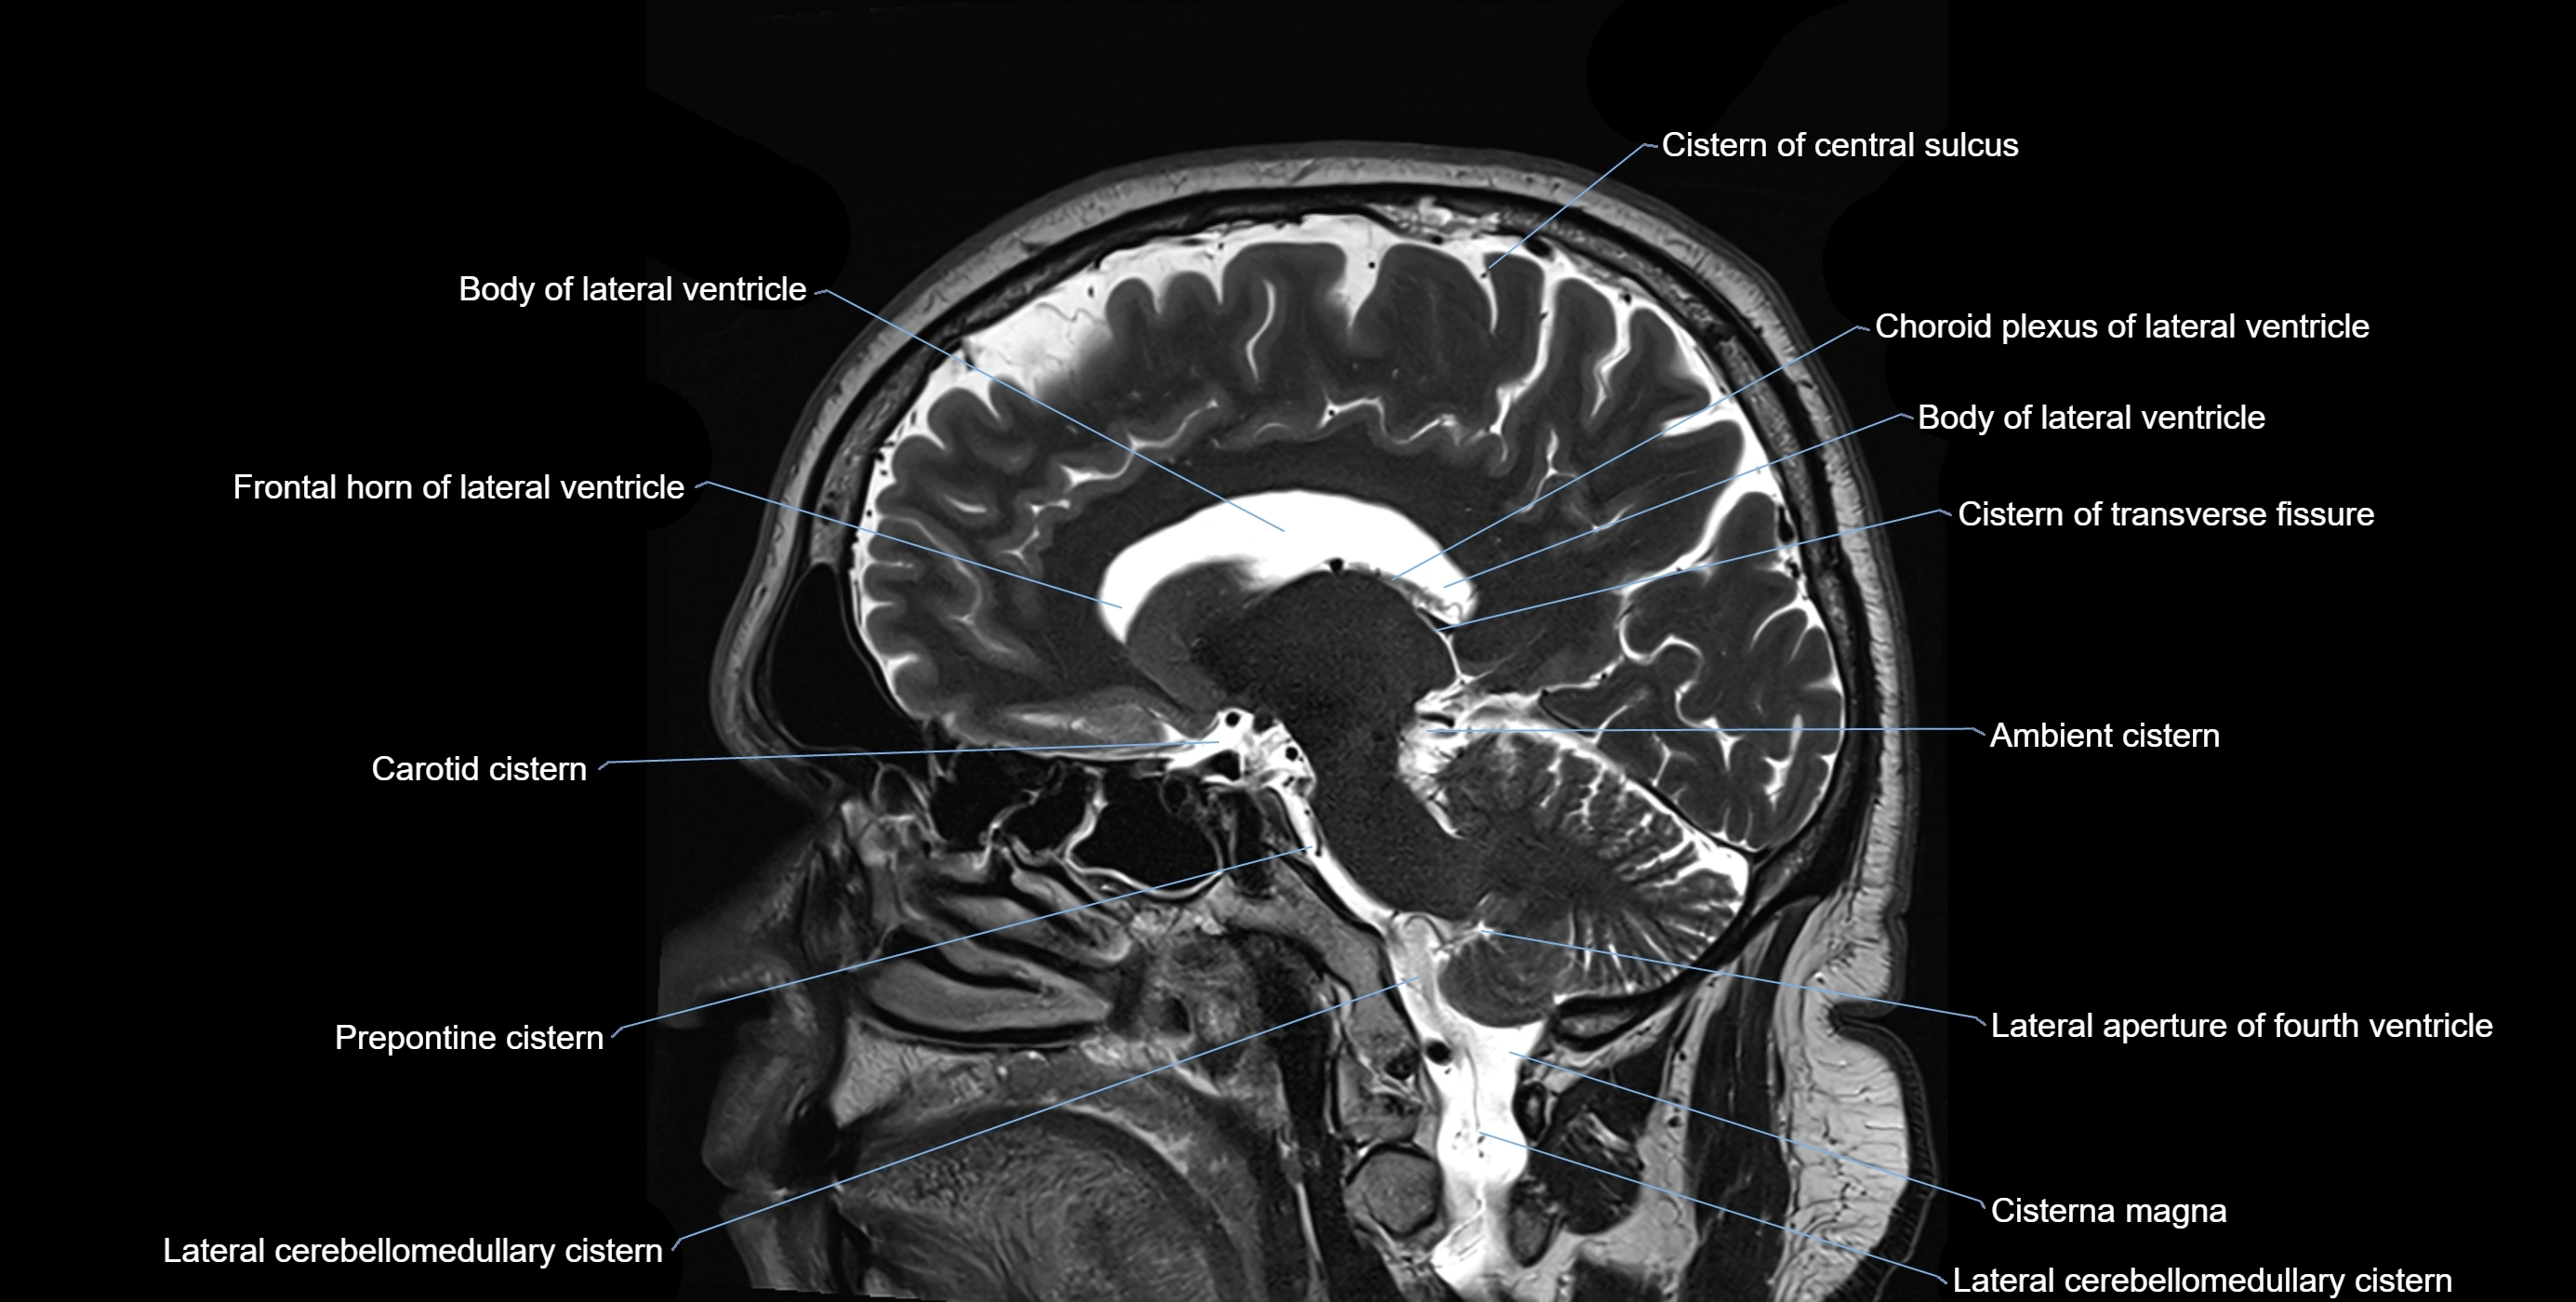

MRI images

image